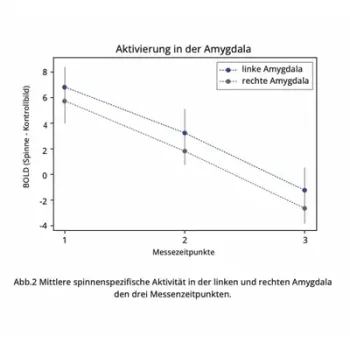

Already after a single Mind Switch® Fear & Phobia App application of 100 minutes, there was a significant reduction in four brain areas, including the amygdala (main fear center in the brain), by an average of 79%.

This effect increased in the second phase of the test and extended to 6 brain areas.

"After repeated use (Total 5 hours per personon average, spread over 4 weeks) of the Mind Switch® Fear & Phobia App, a strong reduction in the response to images of spiders was demonstrated in brain areas usually strongly associated with phobias: In the right amygdala, average activity was reduced by 117%, and in the left amygdala by an average of 145%. In the visual areas of the brain, there was a reduction from 8 units to an average of -1.6 units, in somatosensory-motor regions from 15.1 to - 2.8 units, in the parietal lobe from 8.6 to -5.3 units, and in the cerebellum from an average of 12.2 to 2.7 units. In summary, these results clearly indicate that in people suffering from phobias, a significant reduction in brain activity is observed with repeated use of the app. And this is in brain areas associated with anxiety."

Study results presented graphically

Amygdala